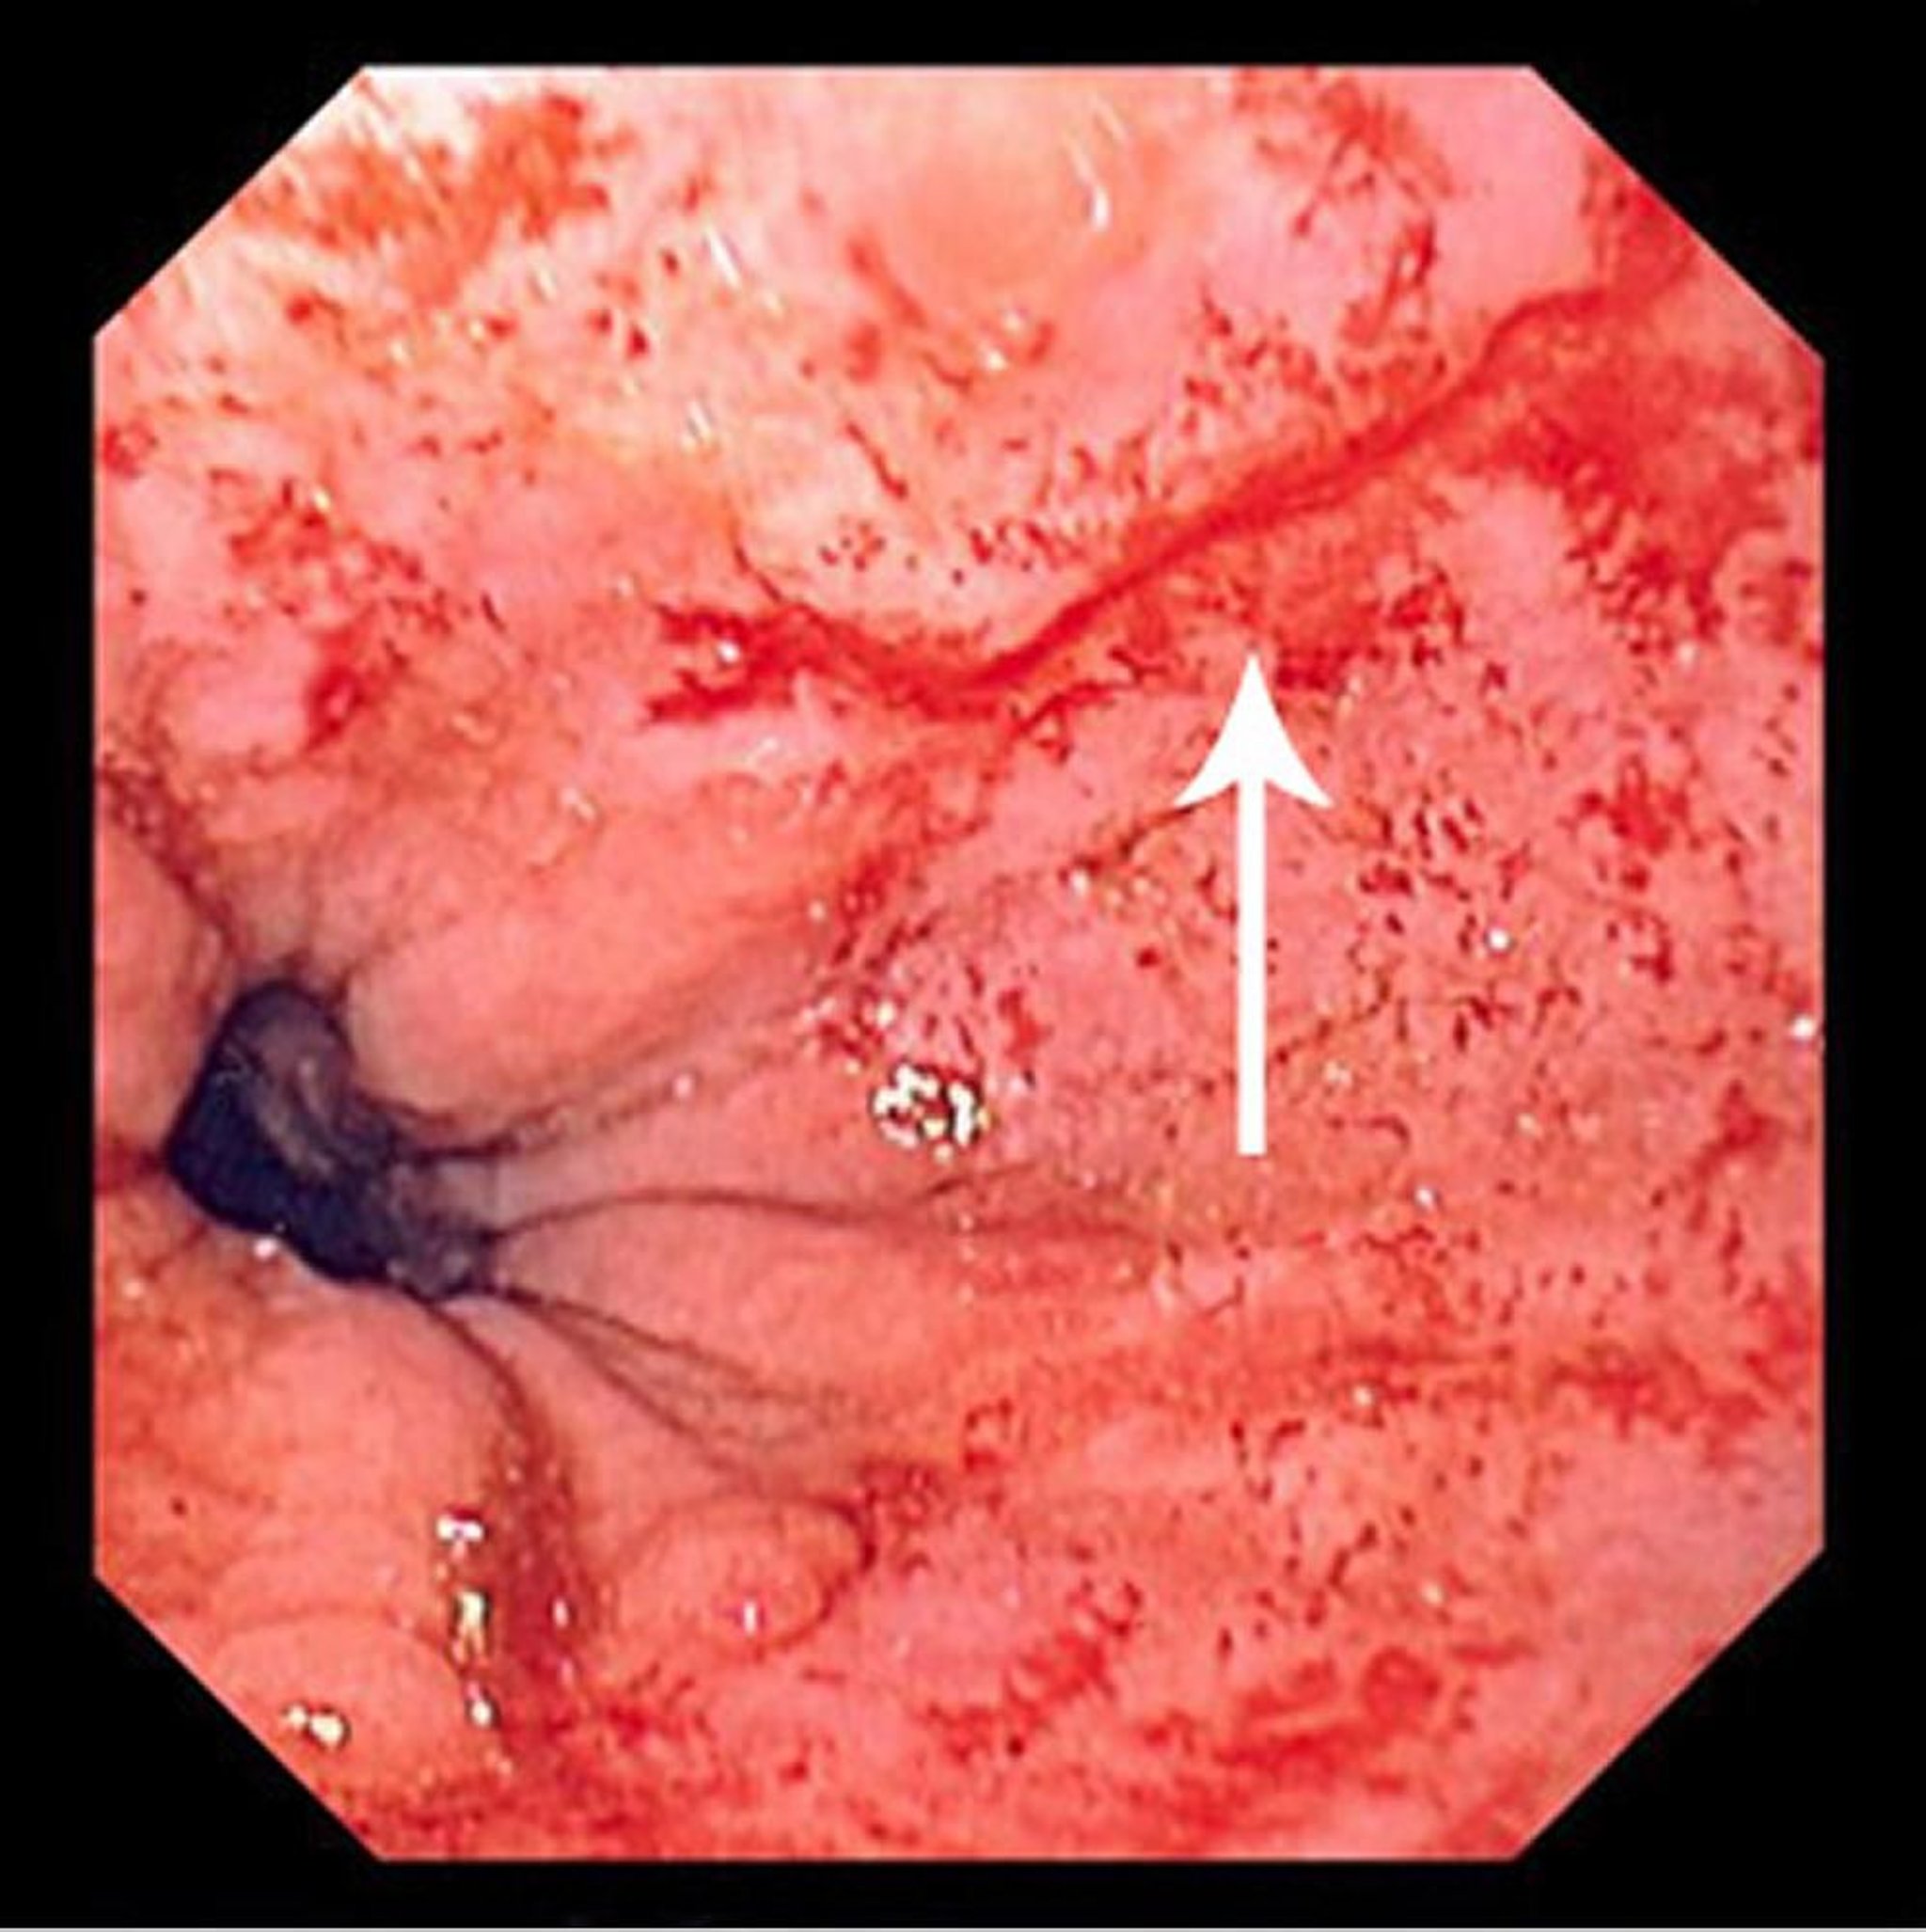

تمزق مالوري-وايس

تُظهر هذه الصورة تمزقًا رفيعًا بحسب مالوري-وايس (اتجاه السهم).

Photo provided by David M.Martin, MD.